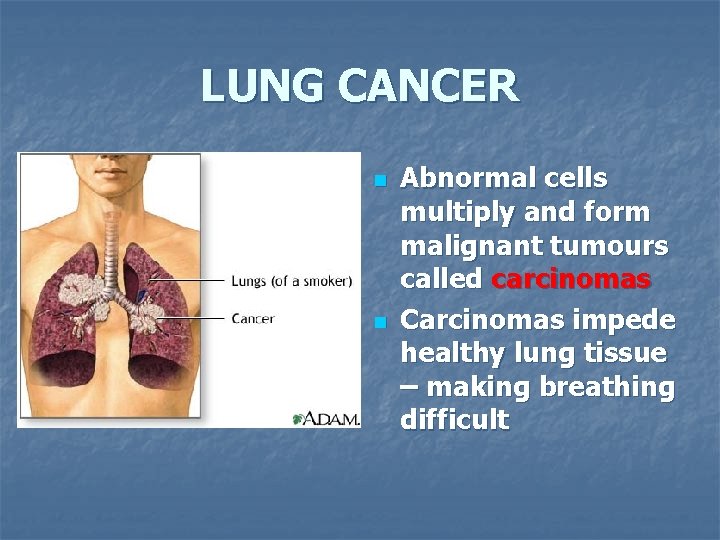

Normal Lung vs. Cancerous Lung

LUNG CANCER n n Abnormal cells multiply and form malignant tumours called carcinomas Carcinomas impede healthy lung tissue – making breathing difficult